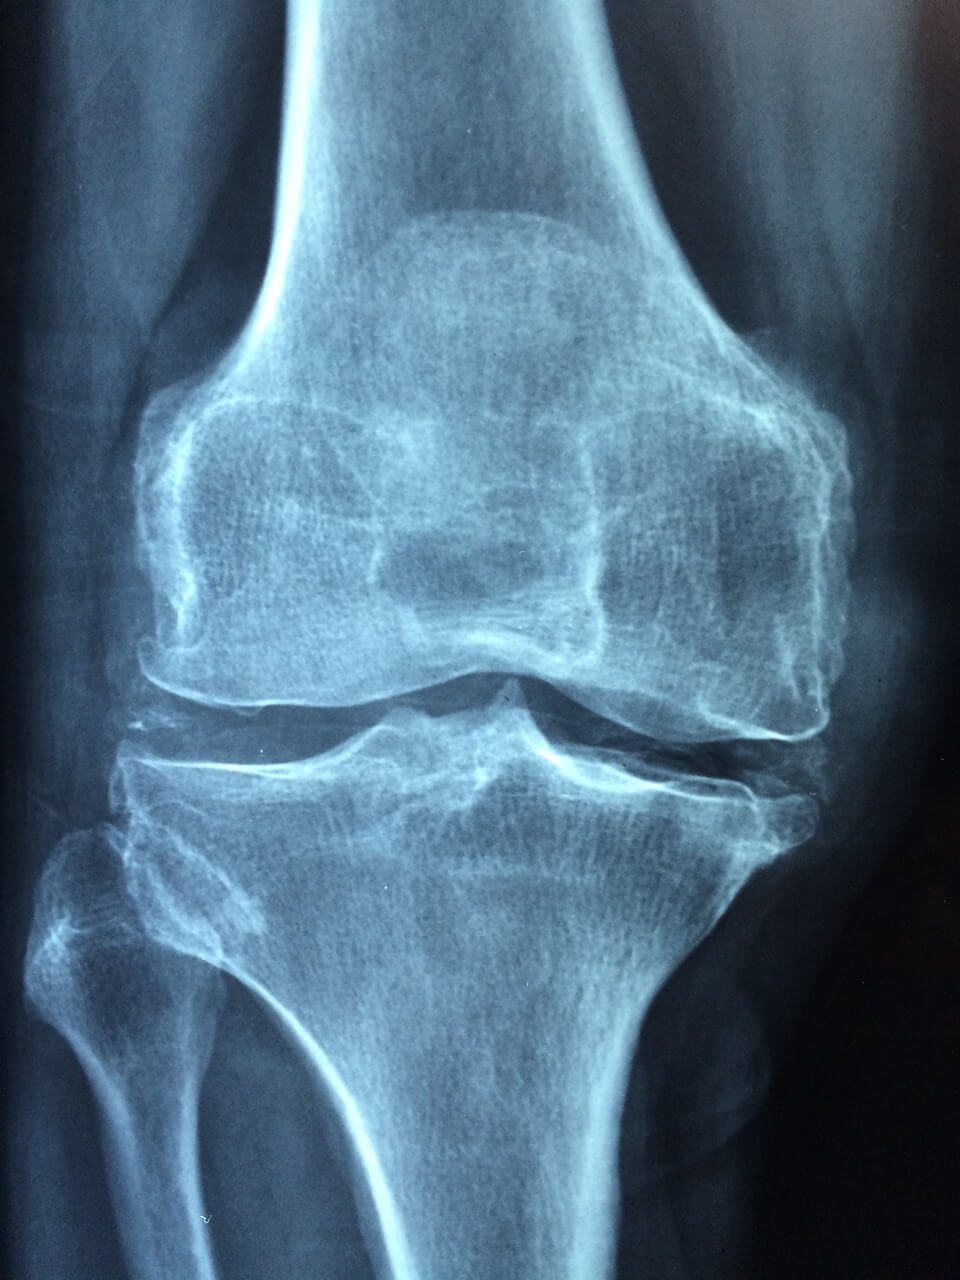

1️⃣ 무릎인공관절 로봇수술 평균 비용

✅ 무릎인공관절 로봇수술 비용은 일반 수술보다 조금 더 높은 편이에요.

평균적으로 보면, 일반 인공관절 수술: 200~300만 원대 (건강보험 적용 후 본인부담)

● 로봇 인공관절 수술: 약 400만 원~600만 원대 (추가 비용 포함)

✅ 로봇수술 비용 중 **'로봇 사용료'는 비급여 항목**이기 때문에 병원마다 금액이 다를 수 있어요. 일반적으로 150만 원~250만 원 정도의 로봇 추가 비용이 발생합니다.

✅ 한쪽 무릎만 할 경우와 양쪽을 동시에 수술할 경우에도 비용이 크게 달라질 수 있으니, 병원비 정보 공개 사이트에서 미리 병원별 평균 비용을 조회해보세요.